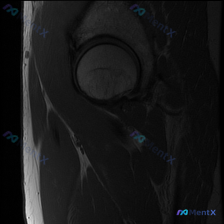

髋关节MRI单帧T1冠状位:盂唇病变能看出来吗?

最近看到一个髋关节MRI病例,提供的是单帧T1冠状位影像,临床怀疑盂唇病变。但T1序列对软组织的分辨率有限,尤其是对盂唇这样的结构。大家基于这张影像,对盂唇病变的诊断有什么思路?或者有哪些其他的考虑方向?欢迎讨论!